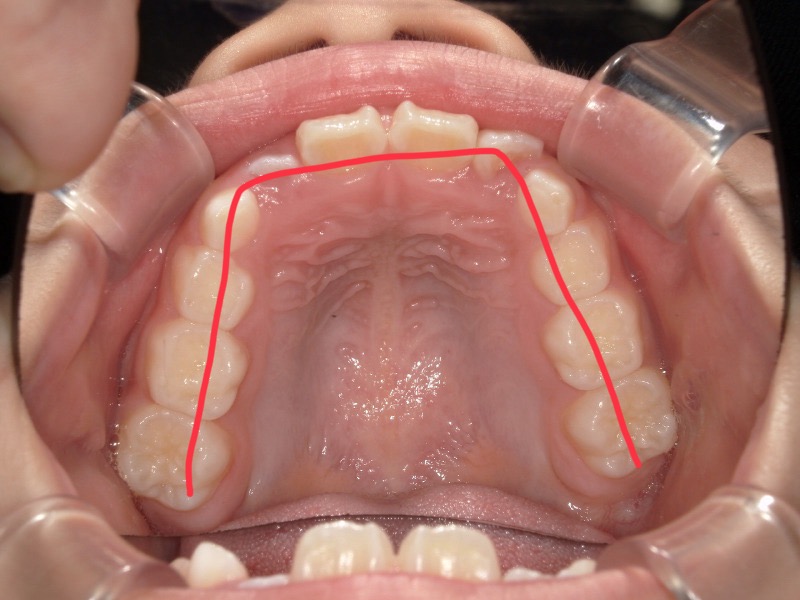

2度目の装置

一度装置は外して様子を見ていたのですがまだスペースが欲しいため再度装置をつけました。

丸で囲っている歯が綺麗に入ることを目的とした装置にもなります。

装置が外れる頃には丸で囲った歯は綺麗に並んでいます。